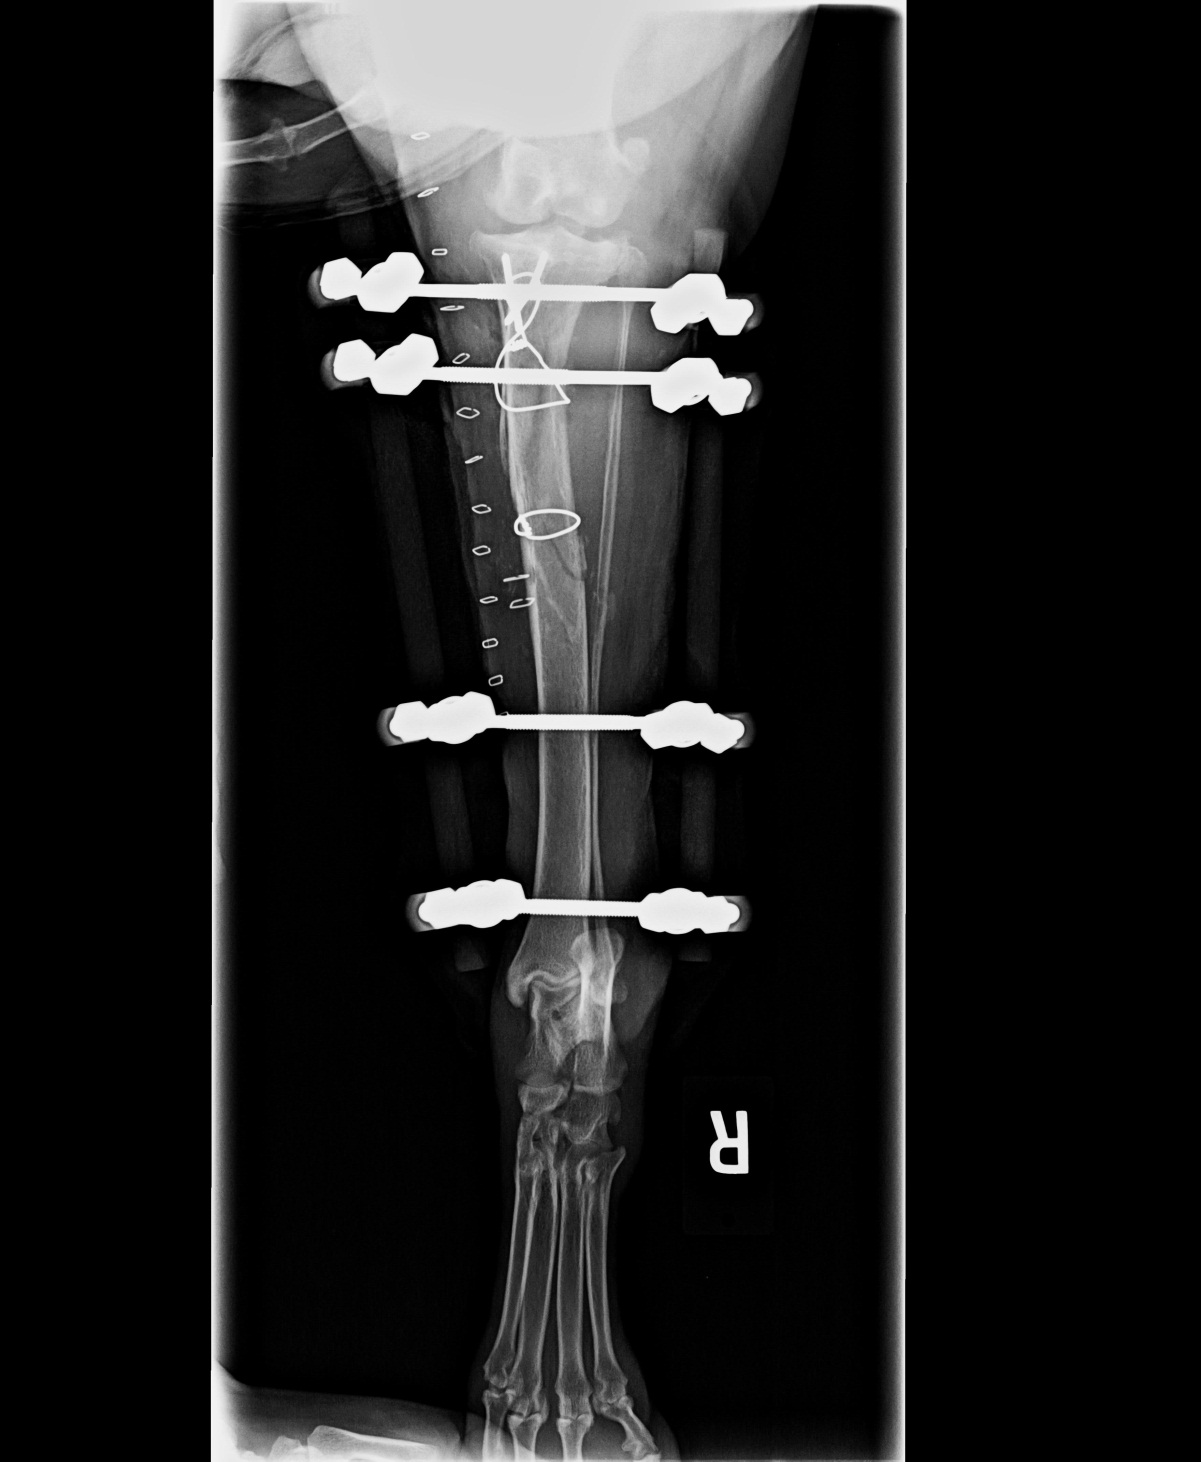

From circlecityvets.blogspot.com

Circle City Veterinary Specialty & Emergency Hospital Oh Those Broken Difference Between Broken Bones This can occur as a partial or complete fracture across the entire bone. in medical terms, a “bone fracture” is the same as a “broken bone”—although people may use the term “fracture” for when a bone is not broken all the way through. There are many different types of fractures and as many different treatments methods for each. Whether. Difference Between Broken Bones.

Circle City Veterinary Specialty & Emergency Hospital Oh Those Broken Difference Between Broken Bones the main difference between a fractured bone and a bone bruise is that a fracture results in an actual break in the bone and a bone. The words are just used interchangeably. a fracture, commonly known as a broken bone, occurs when a bone is subjected to more force than it can withstand. in medical terms, a. Difference Between Broken Bones.